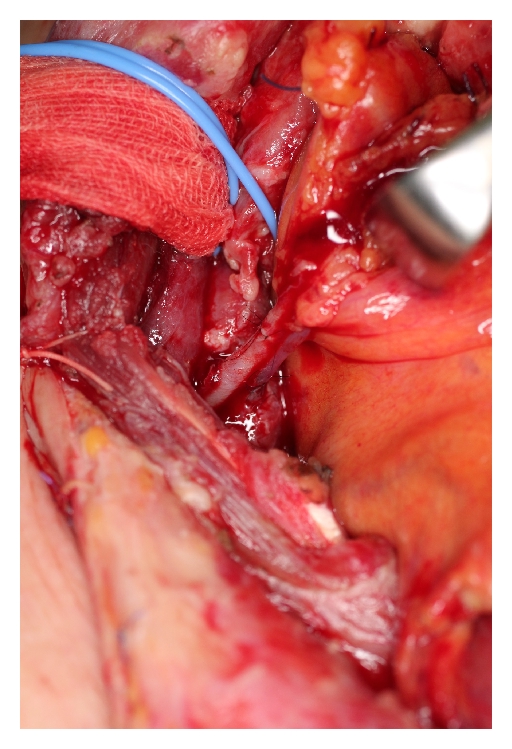

A 62-year-old male underwent surgery for thoracic-cervical esophageal cancer and immediate reconstruction with the retrosternal gastric pull-up technique. The esophagus resection was performed at the level of the 6th cervical vertebra and a bilateral lower segmental neck dissection was performed (nos. 101 to 104) [3]. Therefore, the transverse cervical vessel was exposed in first surgery. Three days after surgery, the patient’s neck exhibited swelling and redness, and the oral side of the pulled-up stomach became necrotic (Figure 1). Thus, 4 days after the primary surgery, the patient underwent debridement of the necrotic tissue and the route of the gastric tube was changed from retrosternal to presternal. The resection of the necrotic gastric tube was 5 cm length, and debridement of necrotic tissue and washing with saline solution were performed. At the same time, immediate free jejunum transfer was performed as salvage surgery (Figure 2). The jejunum was transected at the level of the second jejunal vessel, and the length of harvesting jejunum graft was 15 cm. After trimming of the jejunum graft, the jejunum graft, which was 10 cm length, was placed in the presternal space and joined to the distal end of the cervical esophagus and the proximal end of the residual gastric tube in an end to end anastomosis. The jejunal artery and vein were anastomosed to the right transverse cervical artery and the right internal jugular vein (Figure 3). Because of the short span between first and second surgery, harvesting the free jejunum graft was performed without any difficulty. However, neck dissection during the first surgery caused some adhesion, which resulted in minor technical difficulties during microsurgery. In second time surgery, patient’s vital signs were stable, and no fever or problems in respiratory or circulatory organs were observed. The C-reactive protein level was 22.6 mg/dL, but the white blood cell level was 8.7 × 10³/μL. The patient was able to start oral alimentation 10 days after salvage surgery, and the wound healed completely without complications (Figure 4). Although he died from systemic metastasis from the primary cancer 6 months after the salvage surgery, the patient’s quality of life after surgery, including his food intake, was very good.